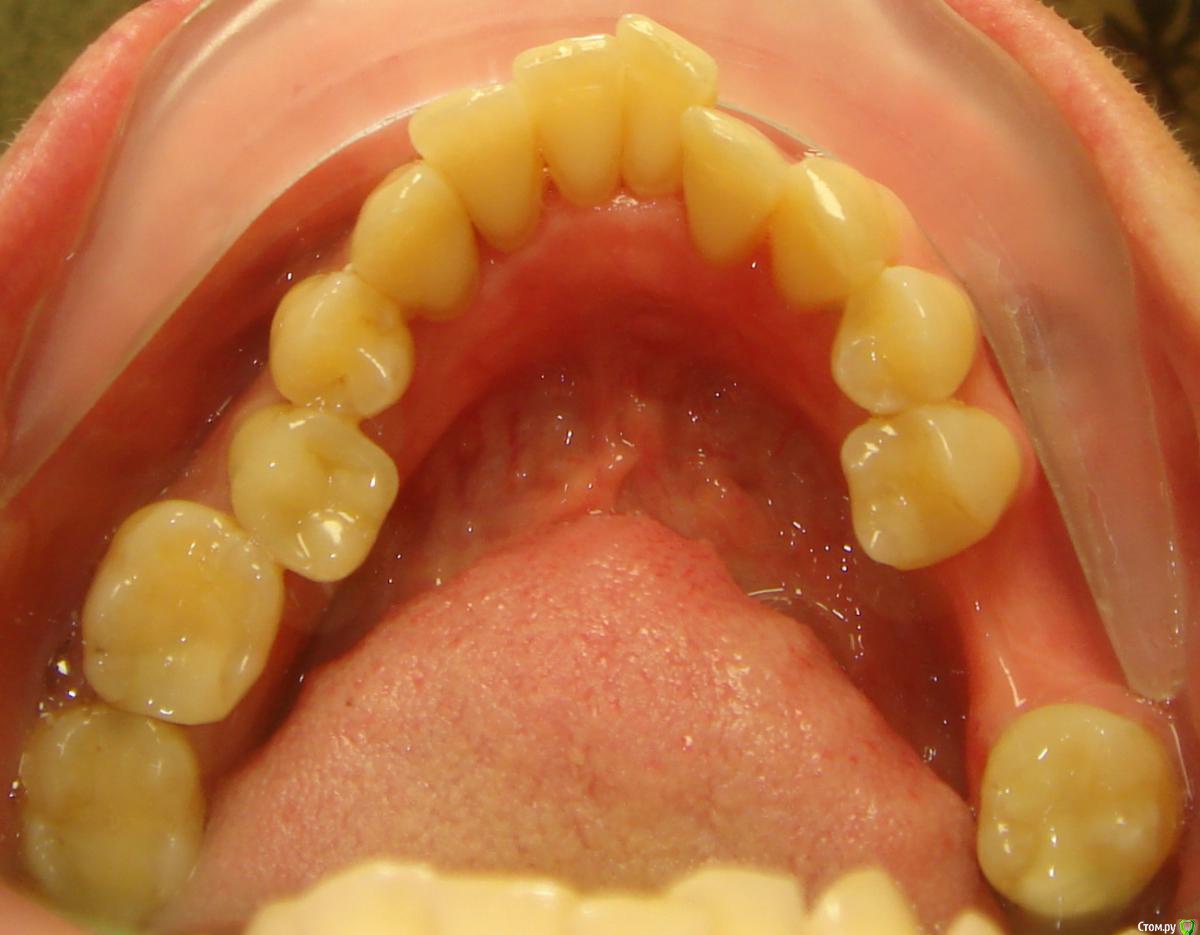

Opdihatop Опубликовано 9 мая, 2016 Поделиться Опубликовано 9 мая, 2016 (изменено) Здравствуйте, коллеги! Хотел бы представить вашему вниманию вот такой вот случай и спросить совета. В принципе, по окклюзии ничего особенного по лечению нет, но вот проблемы с пародонтом (на КТ по кости все заметно хуже, чем на орто), делают невозможным все, продуманные мной варианты. Может у кого-то было что-то подобное? Может поделитесь советом, а то помочь человеку надо, а я в тупике. Буду заранее очень благодарен за помощь! Изменено 9 мая, 2016 пользователем Opdihatop Ссылка на комментарий

Yana guapa Опубликовано 12 мая, 2016 Поделиться Опубликовано 12 мая, 2016 показаний к сарпе здесь нет. дать разобщение и перебросить боковые зубы кросс тягой. внизу бы не удаляла. на самолигах итак места достаточно будет. ну максимум стриппинг. были такие пациенты, что думала зубы с лигатурами вылетят ... но ничего! к концу лечения укрепились даже! все на месте! просто у таких пациентов еще нежнее надо 1 Ссылка на комментарий

Opdihatop Опубликовано 12 мая, 2016 Автор Поделиться Опубликовано 12 мая, 2016 (изменено) И что, кросс тяги и простое расширение на самолигах не вызовет, при таком пародонте, полного разрушения системы (я про кость)? Изменено 12 мая, 2016 пользователем Opdihatop Ссылка на комментарий

Yana guapa Опубликовано 13 мая, 2016 Поделиться Опубликовано 13 мая, 2016 1) Здесь главное, что волнует пациентку, это создание места под 13 зуб. Да, она согласна корректировать все остальные проблемы, но не пойдет на лечение, если "ее" цель не будет достигнута. И да, я понимаю, что идеала тут достичь у меня не получится. под 1.3. зуб место создадите без проблем. Но если Ваша пациентка мечтает о голливуде (может еще и о новом пародонте?) , то лучше ее вообще не брать. Пусть радуется хоть тому, что вообще можно слепить. 2) Так уж сложилось, что кросс-эластиками я не так уж много работал, как то пациенты не подворачивались. По-этому позвольте в связи с этим вопрос: а не навредит ли нам тут вестибулярный наклон верхних моляров, который несомненно возникнет за счет тяги (они наклонены орально незначительно)? Да, я понимаю, что и нижние наклонятся орально, но все же. у вас не будет чистого вестибулярного наклона верхних моляров, потому что помимо кросс-эластиков у вас будут хорошие расширяющие дуги, придающие нужную форму зубному ряду. плюс кросс-тяги. и конечно хорошее разобщение. 3) Почему Вы против, пусть даже не сарпе, так хоть послабления небного шва в этом случае? С трудом верится, что в этом возрасте, пусть даже на самолигах, получится получить стабильное расширение. если Вам там хочется поставить RPE поставьте) но вы всегда можете это успеть сделать, в случае неудачи кросс тяг. заранее обговаривается. (тем более это дополнительные финансовые траты) 4) Я встречал в литературе успешное применение, при подобном пародонте, дистализации на в/ч при непрямом анкораже на м/и. Подобное лечение (с нормальной костью) неоднократно производил и успешно. Как Вы считаете, рискнуть или успех маловероятен? а что Вы дистализировать здесь хотите? Ссылка на комментарий